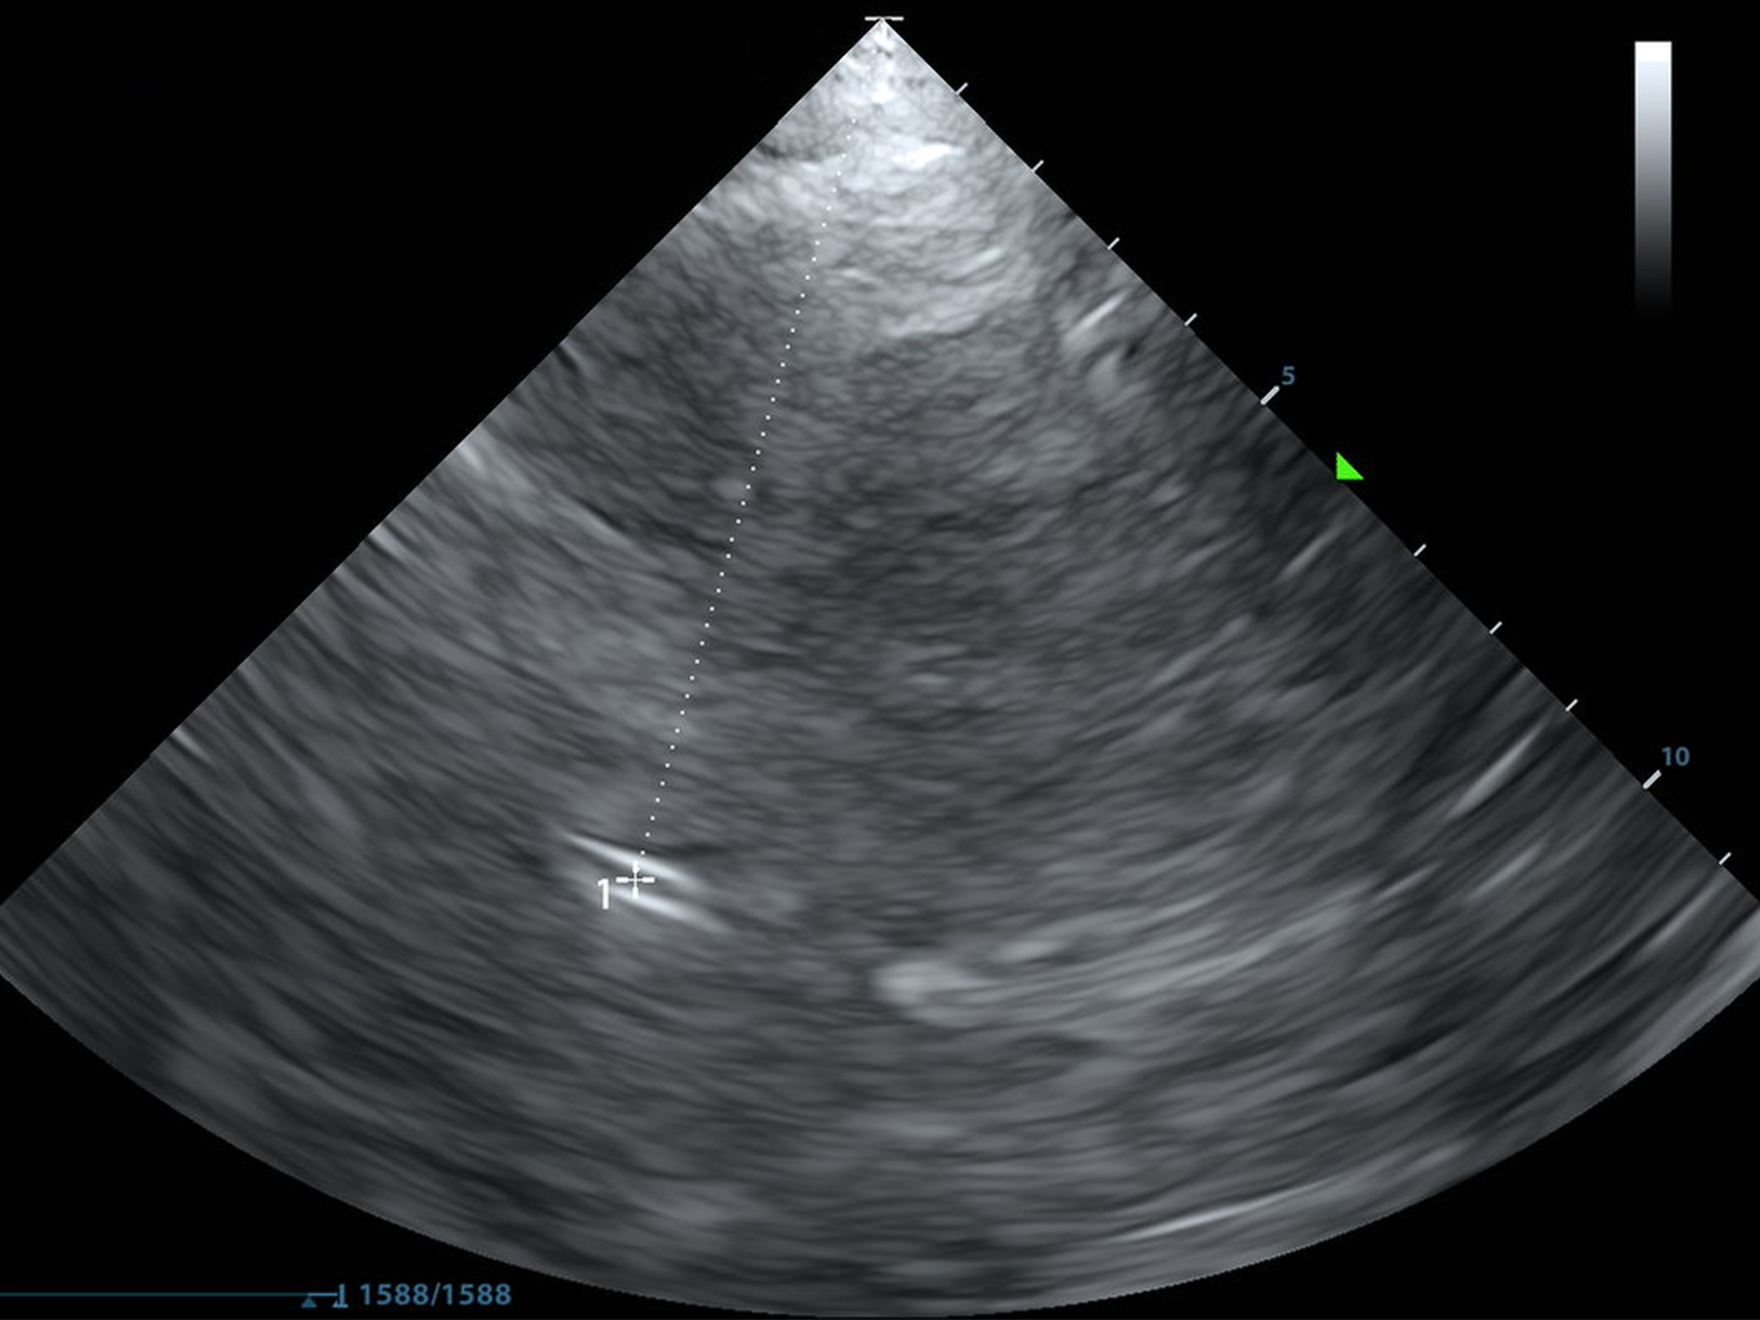

If you can only recognize one thing on the screen aside from skull, recognize the third ventricle.

Now that you found the midbrain/mesencephalon, gently fan your probe cephalad about 10 degrees. Micromotions.

This is the Diencephalon Plane, where the dark thalami surround that sweet, sweet third ventricle like a rain cloud.